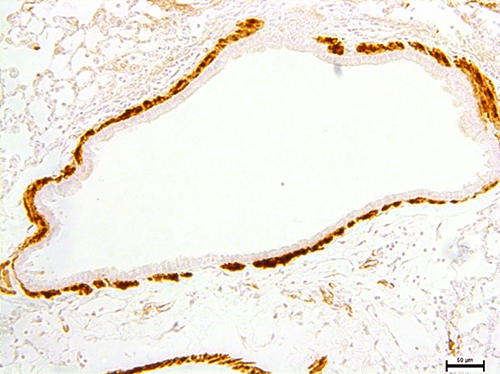

Airway Smooth Muscle Dysfunction in Cystic Fibrosis

One understudied cause of lung disease variability in CF is airway smooth muscle dysfunction. People with CF often develop an “asthma-like” disease with excessive airway constriction in response to stimuli. This can cause worsening lung function, coughing, and increased rate of pulmonary exacerbations.

In our lab, we use animal and cell culture models to better understand how loss of CFTR function triggers alterations in airway smooth muscle behavior. We have found that airway smooth muscle cells in CF react abnormally to TGFβ, becoming more sensitive and more likely to spasm.